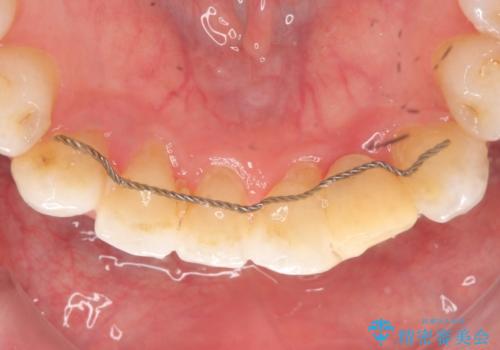

左下123番のブリッジになるが、左下1番と3番の歯軸が合っておらず神経治療が必要になる可能性があるため部分矯正を提案したところ、希望されなかったため、そのままの歯軸でオールセラミッククラウンによる補綴を行いました。

今回用いたオールセラミッククラウンはジルコニアフレームという白い素材の上にセラミックを盛っているため、審美性が非常に高いのが特徴です。

また、ジルコニアは人工ダイヤモンドの材料にも使われているほど高い強度を持っており、そのためオールセラミッククラウンは審美性だけでなく、奥歯やブリッジの補綴も可能とするクラウンです。